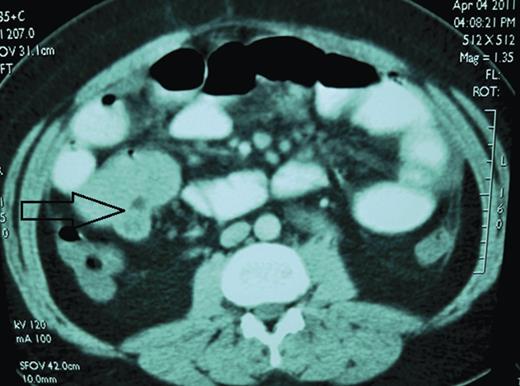

A 26-year-old male patient, previously healthy, presented to our ER complaining of diffuse colicky abdominal pain of one week duration. He also reported nausea, two episodes of non-bilious vomiting and a two-day history of constipation and obstipation. No fever or chills. He denied any past surgical history. His vital signs were all within normal limits. On physical examination, his abdomen was tender, distended and tympanic on percussion. Bowel sounds were hyperactive. DRE showed empty rectum. All his lab tests were normal except for mild leukocytosis. Plain abdominal film showed two air-fluid levels. A follow-up CT scan of the abdomen and pelvis showed small bowel obstruction and a 5 × 5 cm mesenteric mass (Fig. 1). Another mass of 3 × 3 cm was also noted. The patient was referred for surgical management.

The 26-year-old man. Axial contrast-enhanced CT scan shows 5 × 5 cm small bowel mass (arrow). Operative findings confirmed ileoileal intussusception.